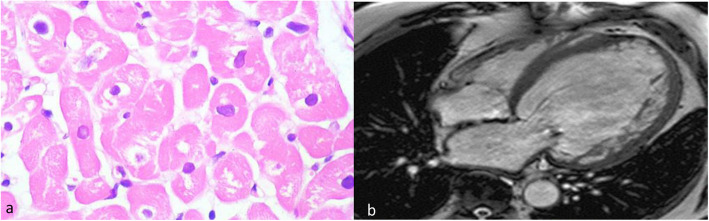

Fig. 2.

a Endomyocardial biopsy of the proband showing hypertrophy, variable nuclear enlargement with sarcoplasmic vacuolar degeneration of the myocytes, and absence of inflammation. b Cardiac magnetic resonance imaging of the proband with ejection fraction 14% and dilated thinning out of the left ventricle

A 19-year-old male was diagnosed with dilated cardiomyopathy. After 12 months, the patient was referred to AIIMS New Delhi with shortness of breath and was admitted to AIIMS ICU. His blood pressure was 94/52 mmHg and heart rate 73 beats per minute at the time of admission. NTproBNP, TropT, and CRP levels at the time of admission were 1881 pg/ml, 11.1 pg/ml, and 3 mg/ml, respectively. SGOT and SGPT levels were 76 and 109 units/l, respectively. The patient also had a history of celiac disease. Echocardiographic screening showed severe left ventricular systolic dysfunction with an ejection fraction of 14%, and electrocardiogram showed left bundle branch block (LBBB) (Fig. 1). The patient had no evidence of inflammation which was confirmed by endomyocardial biopsy and cardiac magnetic resonance imaging (Fig. 2). The patient was treated with steroids, IV immunoglobulins, and IV inotropic agents like dopamine and dobutamine at admission and was finally discharged after being stabilized. The patient was then put on diuretics, carvedilol, and sacubitral-valsartan and was advised to undergo a next-generation sequencing which showed heterozygous variant c.1900C>T in the RBM20 gene leading to a missense variant of amino acid 634 (p.Arg634Trp). The patient was readmitted after a month and was listed for heart transplantation but had a sudden cardiac death after 3 months.